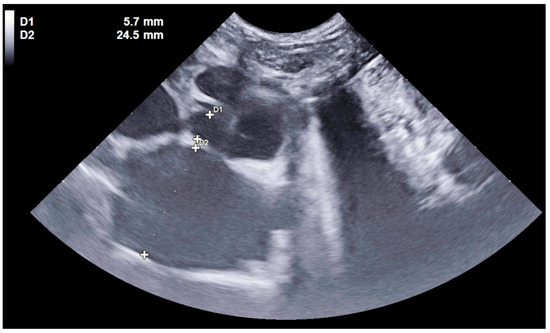

3.3. Results for Cats in Group C—Cardiac Origin

3.5. Results for the Cats in Group N—Neoplastic Origin